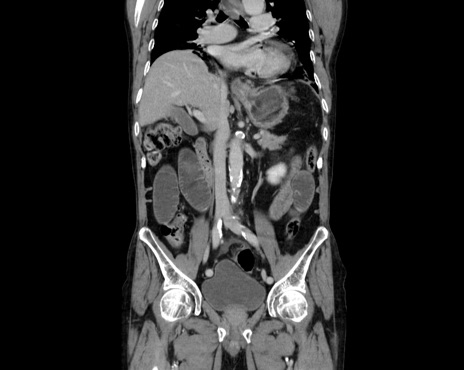

症例26(冠状断像)

【症例】80歳代男性

【主訴】嘔吐

【現病歴】昨晩2回嘔吐あり、今朝になっても嘔吐あり。来院。

【既往歴】胃潰瘍

【身体所見】意識清明、BT 37.6℃、BP 166/95mmHg、HR 100bpm、SpO2 97%、腹部:平坦・軟、腸蠕動音聴取良好、圧痛なし。

【データ】WBC 21900、CRP 1.4